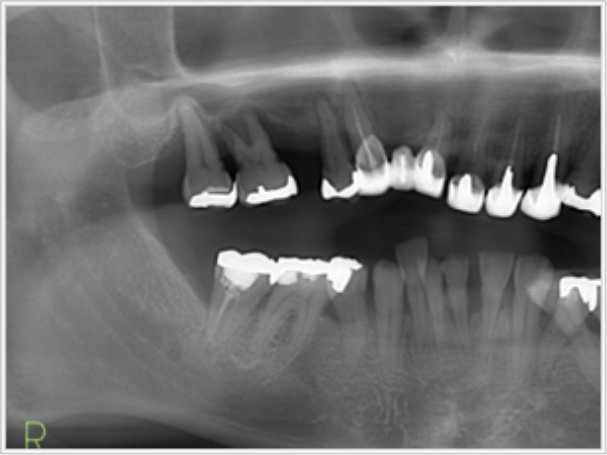

上顎全部欠損

- 治療期間

- 7ヶ月間(インプラント入れてから完成まで

プラスチック

・奥歯(銀歯)

計8本 240万円(税込)